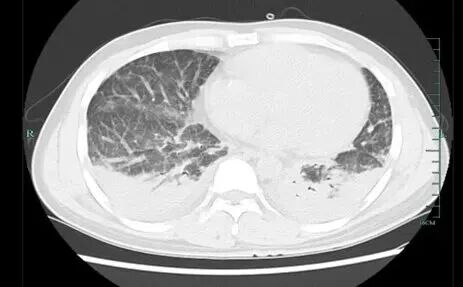

經(jīng)過檢查,壯哥的胸部CT顯示雙肺存在彌漫性病灶,血氧飽和度不足70%。醫(yī)生診斷其為重癥肺炎、I型呼吸衰竭,并表示若再拖延可能危及生命。隨后壯哥被安排住院治療,通過基因檢測,最終確定致病原因為馬爾尼菲籃狀菌。

壯哥的肺部情況